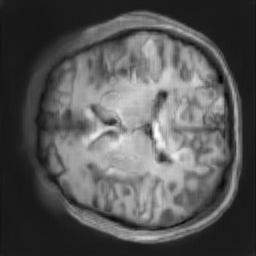

The study utilizes three 3D datasets, namely the GSP dataset[3], the LIDC-IDRI dataset[1], and the dataset employed for the Lung Nodule Analysis 2016 (LUNA16) challenge[21] which is a subset of LIDC-IDRI dataset. Samples from generated images at different stages of training are presented in Fig. 2 and Fig.3.

Refer to caption

20000

30000

40000

50000

60000

70000

80000

CRF-GAN synthetic images at different iterations

Figure 2: Synthetic images of CRF-GAN and HA-GAN at different iterations of training on GSP dataset